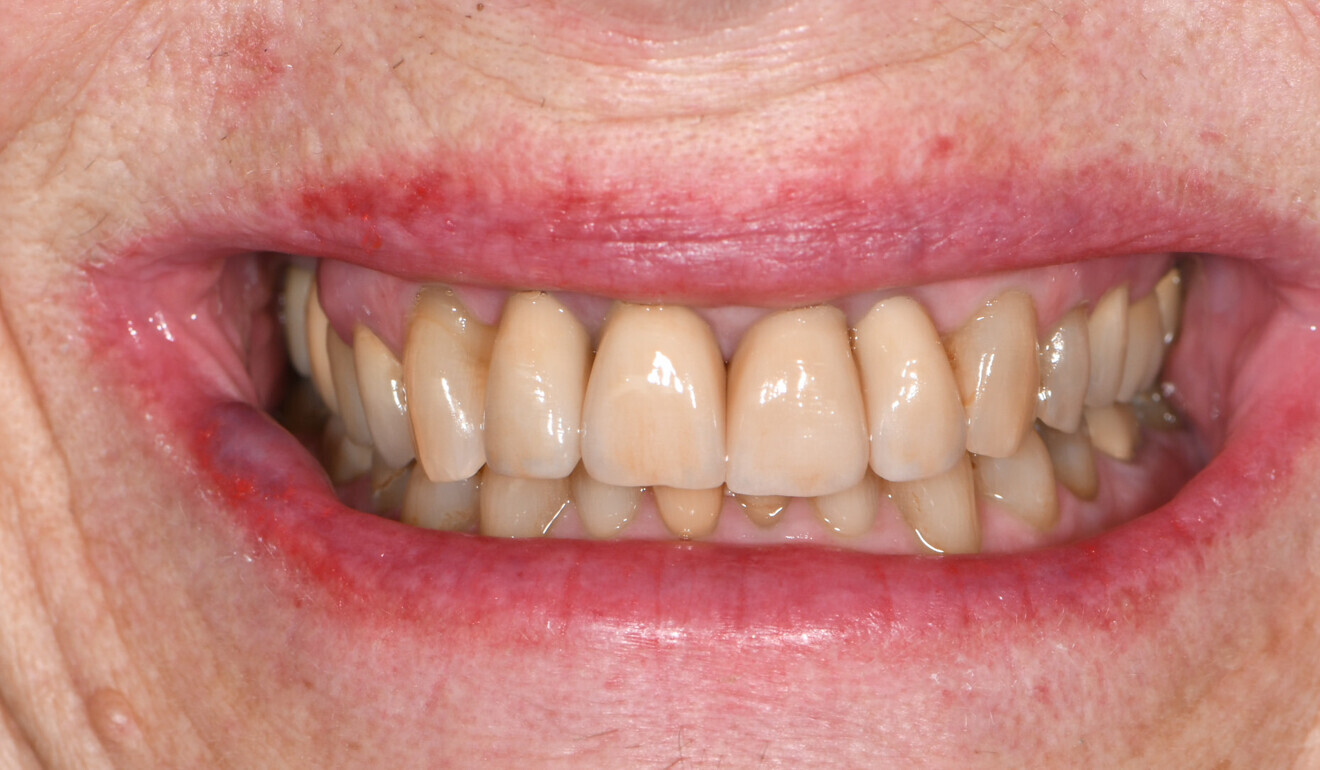

Fig. 13: Immediate treatment outcome, facial view.

Fig. 14: Immediate treatment outcome, frontal view.

Based on the data set of the temporary restorations, four separate crowns—one for the implant and three for the teeth—were designed in full contour. Without any anatomical reduction, the restorations were milled from KATANA Zirconia YML. Based on the evaluation of the temporary restorations, the shade selected this time was Shade A3.5. CERABIEN ZR FC Paste Stain (Kuraray Noritake Dental) was used for external staining and glazing of the surface. The laboratory also cemented the implant-based crown to the gold-shaded titanium abutment (Elos Medtech) with PANAVIA V5 (Kuraray Noritake Dental) in the shade Opaque for an improved masking effect (Fig. 11). In the office, the abutment–crown was screwed on to the implant and the screw access hole closed with composite, and the three tooth-based crowns were then placed using PANAVIA SA Cement Universal (Figs. 12–15).